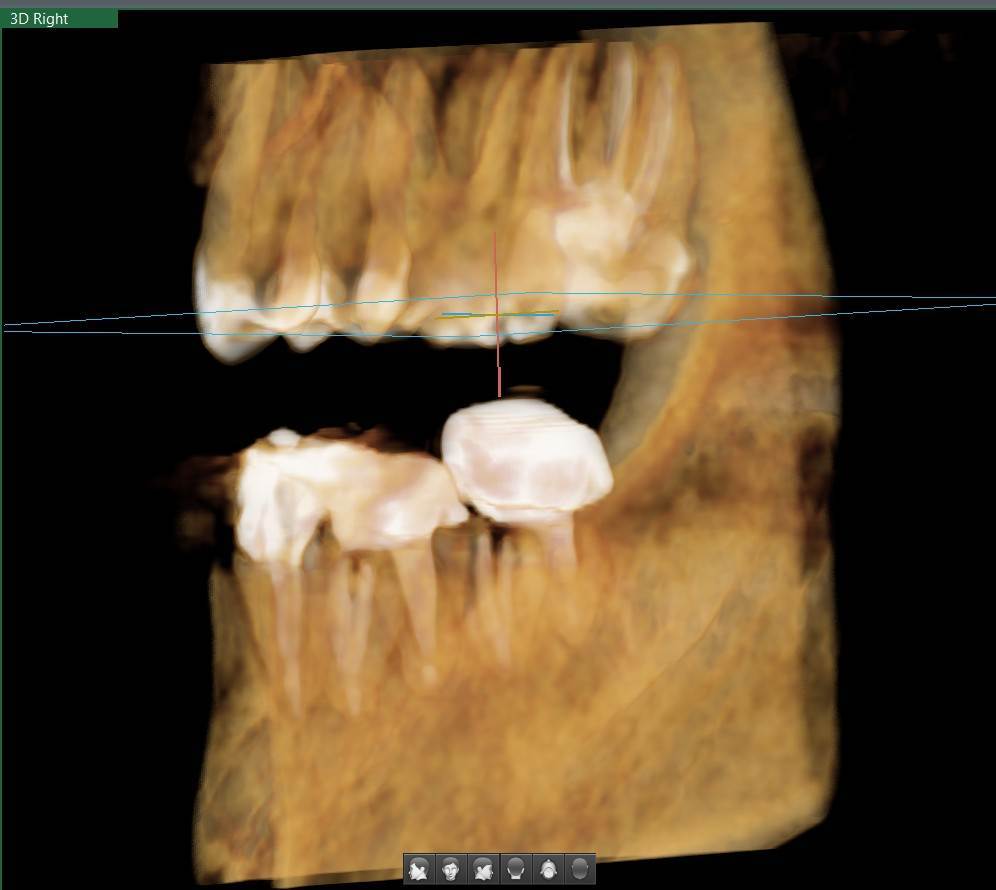

A-V-S Опубликовано 3 марта Поделиться Опубликовано 3 марта Здравствуйте. У меня такая ситуация: В начале января 2026 начал болеть зуб 7ка снизу слева - боль развивалась постепенно - в итоге стало больно жевать. Сделал КТ. Лечащий стоматолог сказал, что это проснулось спящее воспаление, перелечивать каналы зуба сложно - надо сверлить буром и доставать стекловолоконный штифт - надо удалять. В следующие дни открылся свищ и боль ушла. Свищ продолжает быть с периодическим набуханием и сдуванием после выброса гноя белого цвета. Этот зуб лечили с установкой стекловолоконного штифта чуть больше 5 лет назад. Посмотрите, пожалуйста, приложенные снимки и посоветуйте как быть - можно ли перелечить и сохранить зуб ? Ссылка на комментарий

АнтонТЛТ Опубликовано 3 марта Поделиться Опубликовано 3 марта Добрый вечер, лучше выложить несколько срезов этого зуба, либо архив с кт. По представленным снимкам, есть подозрение о наличии трещины между корнями зуба. 1 1 Ссылка на комментарий

red_butler Опубликовано 4 марта Поделиться Опубликовано 4 марта Здравствуйте, Вы выложили не срезы. а реконструкцию. Залейте кт в облако и скиньте сюда ссылка на скачивание Ссылка на комментарий

Гарриевич Опубликовано 6 марта Поделиться Опубликовано 6 марта Не знаю обрадует Вас это или огорчит, но зуб можно сохранить соседний тоже с воспалением кстати 1 1 Ссылка на комментарий

red_butler Опубликовано 9 марта Поделиться Опубликовано 9 марта В 03.03.2026 в 22:49, A-V-S сказал: можно ли перелечить и сохранить зуб ? можно Ссылка на комментарий